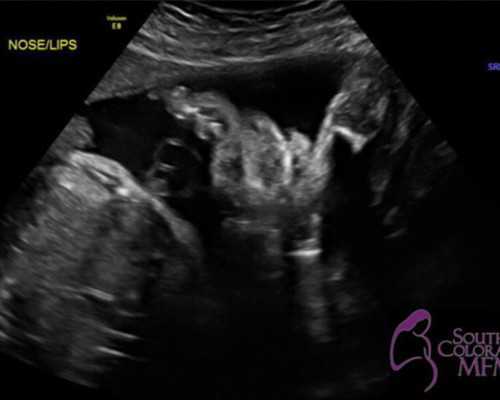

1、确保宝妈的孕期达到了7周或者7周以后,并且B超检测出宝妈的胚芽长度达到了10mm或者10mm以上。

要知道孕妈妈如果太早的就去医院做B超检查的话,那么是很难看到胚芽的长度的,最后的检查时间就是在自己怀孕的时间已经达到7周的时候,在这个时候去做B超检查是最为合适的。单单只是从胎龄上来讲时间就已经满足了香港验血检查的标准,另外这个时候也可以从B超单上看出胚芽的长度。

如果有的孕妈妈发现自己的B超单上没有出现有关胚芽长度记载的话,那么此时也不用太担心,此时孕妈妈完全可以采用去测量胎儿的搏动,这个检测的方式也是比较准确的。

1、一定要等到宝妈孕期达到7周以后方可进行检测,同时需要在当地的医院B超检测出宝妈的胚芽长度达到了10mm以上。